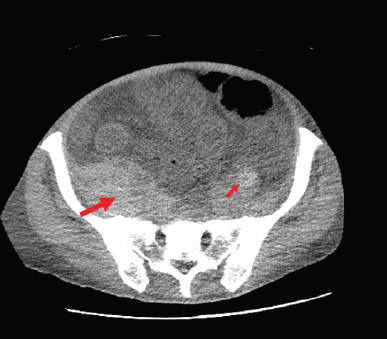

The patient, however, presented to the ER with dyspnoea, fatigue, nausea, generalised abdominal pain and haematuria. Upon imaging, he was found to have a newly-developed retroperitoneal bleed (Figure 2). Initial haematology labs reported severe anaemia with Hb level of 4.5 g/dL (ref 14–18 g/dL), mild leukocytosis of 12.17 k/μL (ref 4.5–11.0 k/μL), and normal platelet count of 202 k/μL. Coagulation studies showed elevated prothrombin time (PT) of 17.9 seconds (ref 12–15 seconds), elevated partial thromboplastin time (PTT) of 104.9 seconds (ref 23–36.0 sec) and international normalised ratio of 1.4. Chemistry results showed acute renal injury with creatinine of 3.6 mg/dL (ref 0.7–1.2 mg/dL and patient’s baseline of 0.9 mg/dL). Patient was initially managed with blood transfusions, intravenous (IV) fluids, IV vitamin K given active haematuria. Mixing studies were ordered to further evaluation of the deranged coagulation panel. Peripheral smear was negative for spherocytosis or schistocytosis. A work-up of the patient bleeding yielded no signs of acute haemolysis (or deep venous thrombosis), fibrinogen levels were normal and patient’s coagulation factors studies were unremarkable, except for severe decrease in his factor VIII activity. Mixing studies revealed prolonged PT and PTT with 1:1 mix correction of PT and no correction of PTT and a 14.2 seconds post-incubation period, pointing towards decreased factor VIII activity. These results were suggesting the presence of a factor inhibitor. Bethesda assay titer was sent and results shown high levels of factor VIII inhibitor which was 13.2 (ref < 0.5) with factor VIII of <1%. Plans for chemotherapy were put on hold at that time and patient was started initially on recombinant factor VIIa (rVIIa), and afterwards prednisone and rituximab were added. The recombinant factor VIIa was given at a dose of 70 mcg/kg with decreasing frequency (initially every 2 hours, followed by every 6 hours and then every 12 hours) and was used in the first 2 weeks of admission, guided by the patient’s haemoglobin. Following that, prednisone was started at 1 mg/kg and was also given for the first 2 weeks followed by tapering course. Given the severity of the presentation, cyclophosphamide and rituximab were considered, however, rituximab was favoured given the patient presentation with haematuria and possible cystitis. The patient received 1 dose weekly of rituximab for 3 weeks at a dose of 375 mg/m2).

Figure 2. CT Abdomen showing severe anasarca and retroperitoneal haemorrhage. The figure shows the bilateral retroperitoneal haemorrhages both right sided (thick arrow) and left sided (thin arrow). It illustrates the asymmetry with right side retroperitoneal haemorrhage being larger in size.